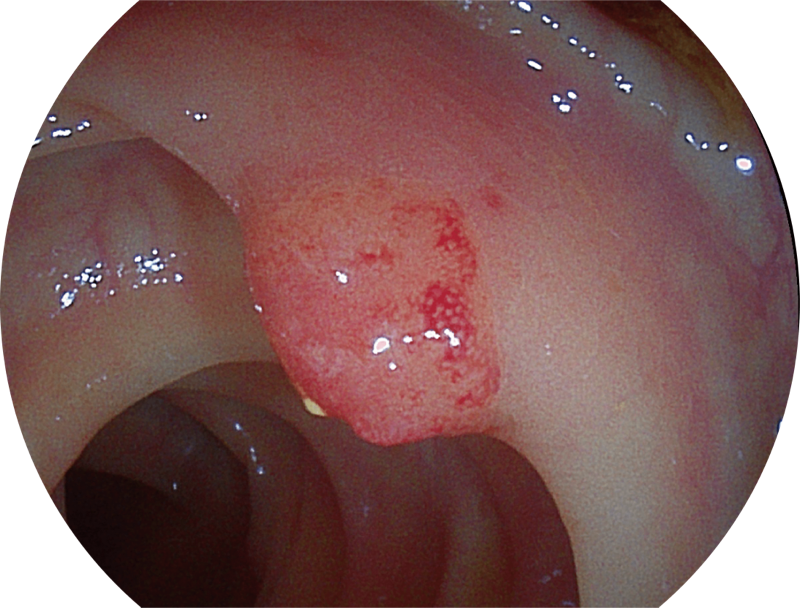

能够凸显黏膜浅层和中层血管轮廓,适用于中、远景观察下的病灶识别和早癌筛查。

(Versatile Intelligent Staining Technology)

能够凸显黏膜浅层血管轮廓和黏膜表面微结构,适用于中、近景观察下的早癌精确诊断。